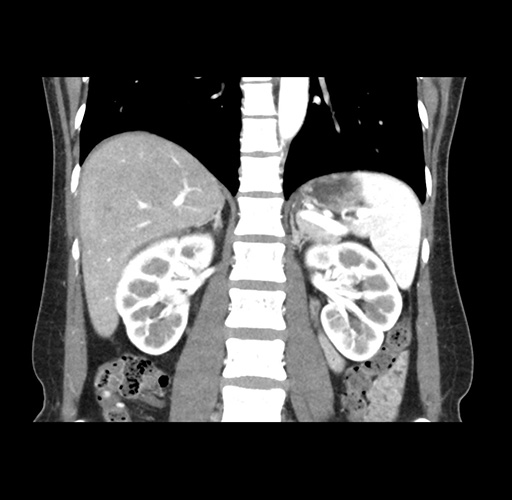

Imaging Analysis

Look through the patient's CT scan to identify any areas of concern for the necessary procedure.

Based on your CT findings, which issue(s) would give reason for "planned slowing down moment(s)" in this case?

Considering a standard left lateral sectionectomy procedure, what step(s) of the operation would you do differently in this case ?